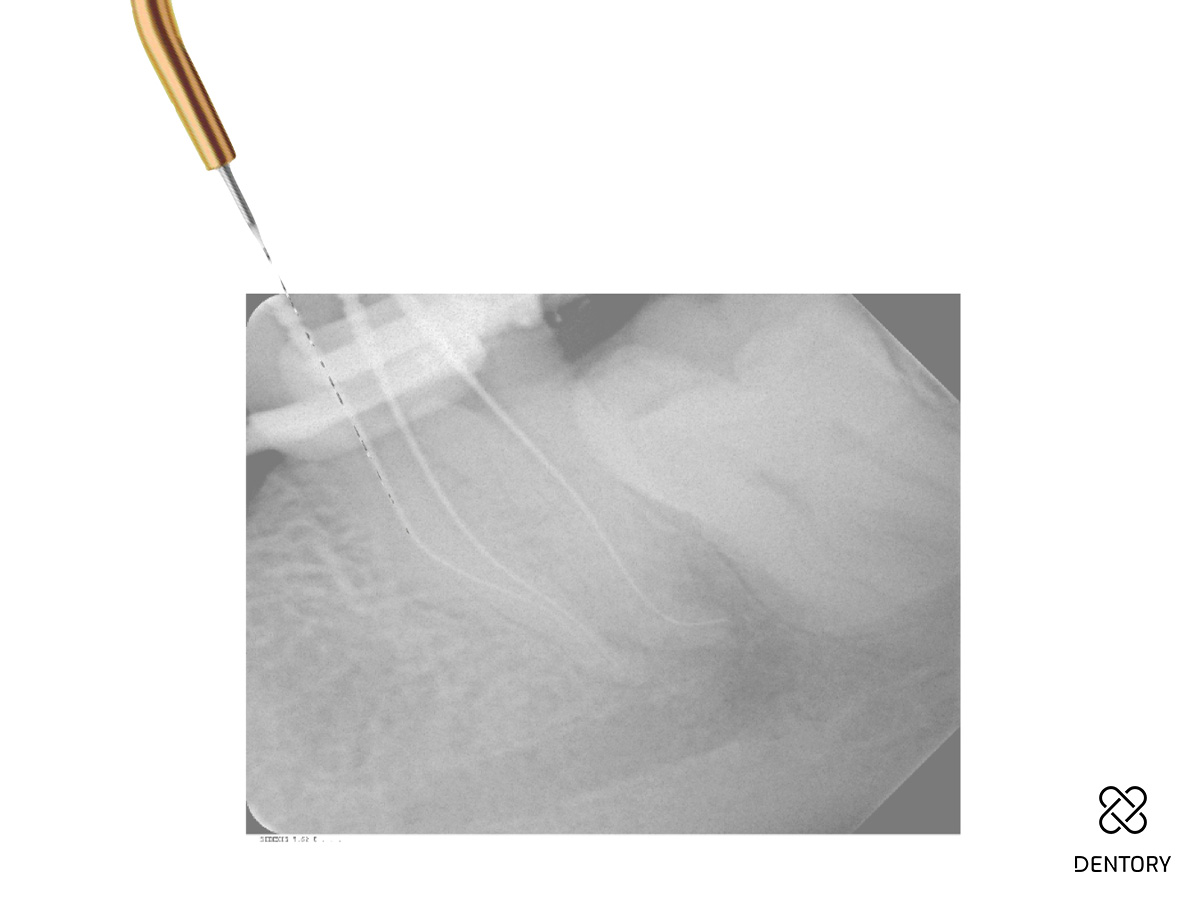

Abbildung 4

Nach jedem Einsatz im Kanal ist die Feile visuell auf Deformationen zu überprüfen.